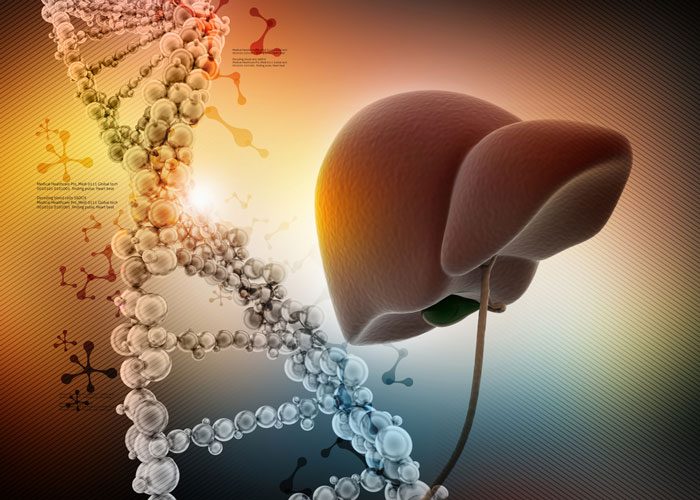

Scientists create advanced 3D liver model mimicking real tissue

Scientists have developed a 3D liver model, known as the periportal assembloid. This model replicates the liver’s complex structure and bile transport system, enabling more precise study of disease progression.